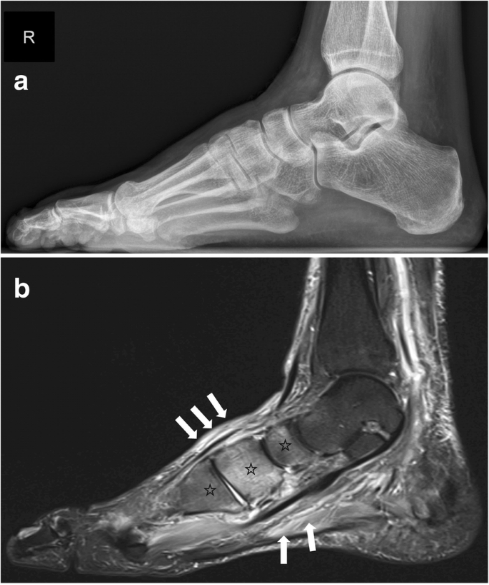

局部肿胀、温度升高;X片和CT检查结果正常;MRI结果显示骨水肿 |

X片和CT检查显示骨碎裂、骨溶解、骨折、脱位 |